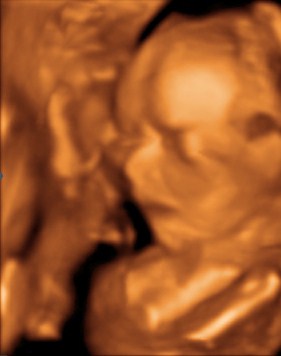

Fantorangen Skrevet 21. mars 2010 Forfatter #406 Skrevet 21. mars 2010 Da er det søndag igjen og dagene flyr synes jeg. I alle fall helgene... I går var jeg og mannen på 3-d ultralyd å så på lille frøkna. Vi har et familiemedlem som er alvorlig syk og derfor ville vi ta litt tidlig 3-d så denne personen også kunne få et inntrykk av babyen. Vi viste at bildene ikke ble helt perfekte fordi hun ikke har så mye underhudsfett på kroppen, men synes at det ikke ble så verst alikevel. Fikk mange bilder og noen videosnutter og hun var veldig villig til å vise seg frem. I tillegg var den som tok ultralyden ikke i tvil på at det er ei jente, så nå er det bare å vaske tøyet vi har arvet... Bilde av lille gullet vårt...